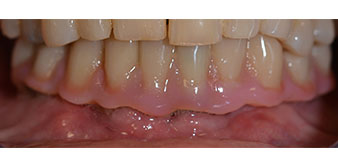

Following the time required for the osseointegration, the final impression of the implants could be performed and the final denture produced accordingly (Fig. 19 and 20). At this point, the dentist and patient were able to decide together whether to use a ceramic or acrylic veneer and a zirconium or metal framework. In this case, Dr. Pascu’s team decided on an acrylic veneer based on the unclear prognosis for the maxillary dentition and the fact that tooth 24 is elongated. This type of veneer is generally considerably easier to adapt and can thus be subsequently altered to reflect the new situation in the maxilla.

Osseointegration

Fig. 19

Implants

Fig. 20